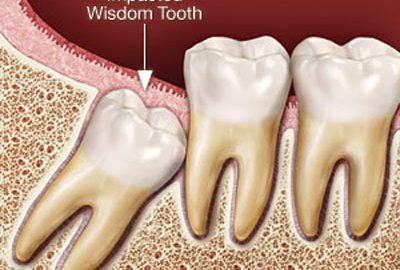

Teeth

Removal of Impacted Teeth

When teeth grow in sideways, emerge only part way from the gum or remain trapped below the gum line, it can...